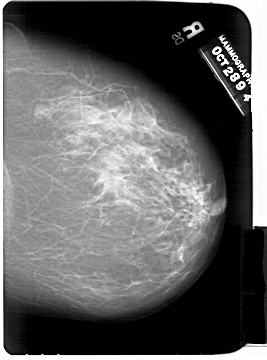

A_1438_1.LEFT_CC

RIGHT_CC LINES 6826 PIXELS_PER_LINE 5056 BITS_PER_PIXEL 12 RESOLUTION 43.5 NON_OVERLAY